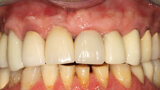

Fig. 12a: A post fracture presenting in the left central incisor, requiring extraction.

Fig. 12b: The occlusal view illustrated the cervical tissue volume and contours.